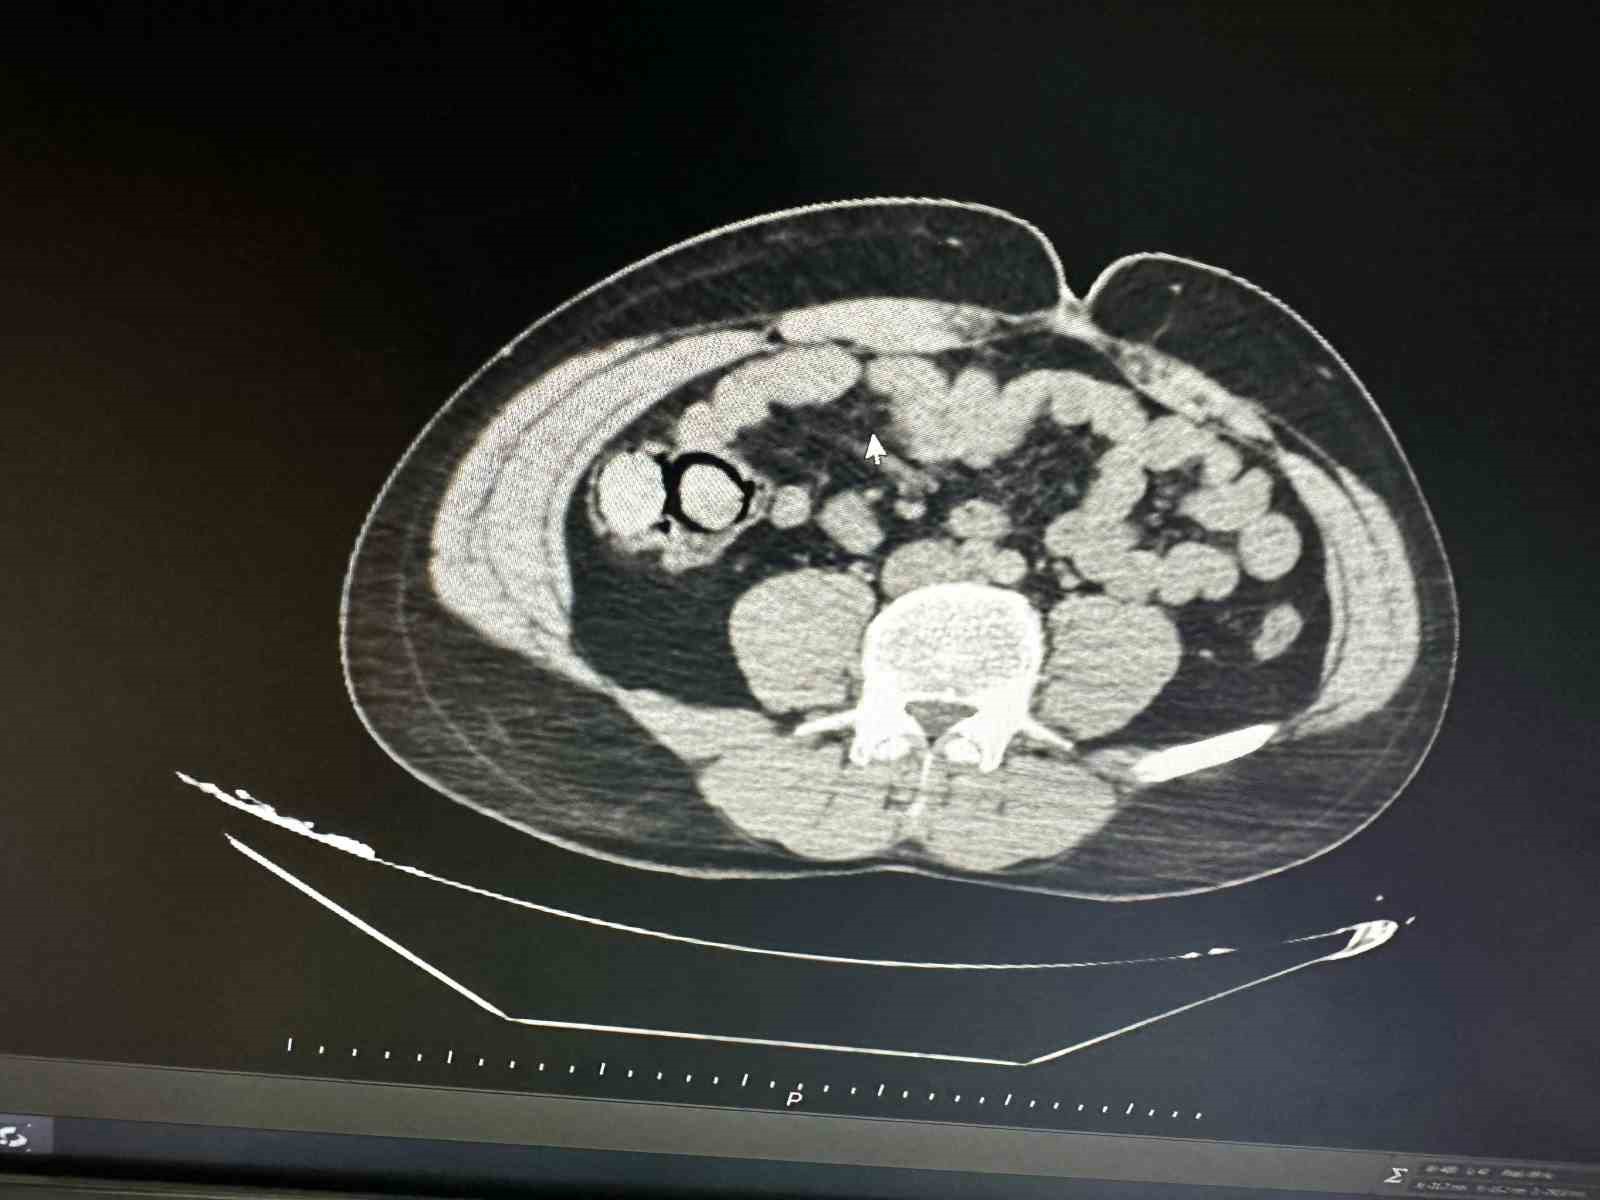

Bingöl’de akıllara durgunluk veren bir olay gerçekleşti. Otobüs yolculuğu sırasında polis ekiplerince durdurulan yabancı uyruklu iki şahsın midesinden 10 parça halinde 113 gram metamfetamin çıktı.

Bingöl Emniyet Müdürlüğü Narkotik Suçlarla Mücadele Şube Müdürlüğüne bağlı narko-timleri akıllara durgunluk veren bir uyuşturucu kaçakçılığını çözdü. Ekiplerin çalışmaları neticesinde otobüs ile Bingöl’e gelen şüpheli yabancı uyruklu 2 şahsın iç beden muayenesinde 10 parça halinde 113 gram metamfetamin maddesi tespit edildi. Emniyetteki işlemlerinin ardından mahkemeye çıkarılan 2 şahıs, uyuşturucu madde ticareti yapmak suçundan tutuklanarak Elazığ Kapalı ceza infaz kurumuna tesliM edildi.